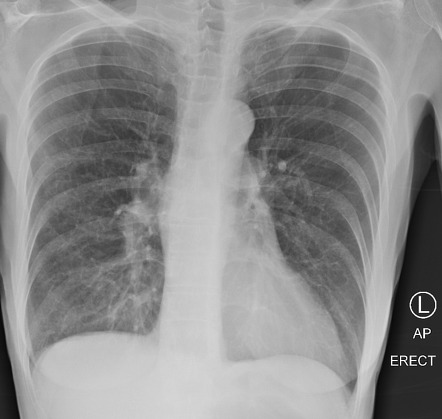

Нормальная рентгенограмма легких: что нужно знать

Раздел: Мудрость в объективе